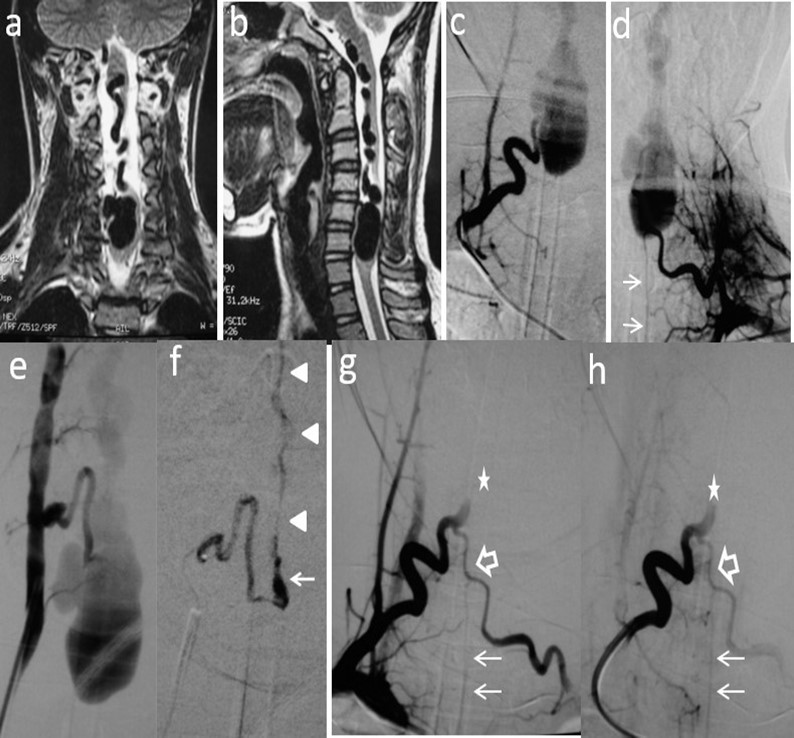

Figure 2.Case # 2: a) Coronal and b) sagittal T2W MRI shows large venous varix compressing ventrally the cervical cord at C5-C6 levels causing moderate central hyperintensity above, and mild below the cervical cord. Ascending convoluting draining veins reach the brainstem. c) d) and e) Angiograms showing right and left arteries of the cervical enlargement as well as a PSA of the right vertebral artery. All of them converge and shunt the varix at the same fistulous point. The ASA branches off the left artery of the cervical enlargement (thin arrows). f) DSA shows the right PSA feeder catheterized proximally. An injection of 30% n-bca in lipiodol was performed reaching the fistulous point (arrow). A thin layer of glue cast is seen in the lateral wall of the ascending vein (arrowheads) g) and h) Post-embolization right ascending cervical artery angiogram showing an arterial blockade at the entry of the fistulous point (star) preserving its anastomosis with the contralateral artery (open arrow). Notice that by reflux, the left artery of the cervical enlargement fills the ASA (thin arrows). Four hours later, the patient suddenly developed quadriplegia probably due to venous and/or ASA thrombosis. Patient lost to follow-up after 2 months.

Two out of 4 patients were diagnosed and studied preoperatively with both spinal MRI and CT scans, 1 patient with MRI and the other patient with CT/CT Angiography with 3D reconstruction. Large and tortuous flow voids with large to giant venous pouches or pseudoaneurysms (3 of our cases - type c) causing compression of the spinal cord were found lying ventrally and, in another one, posterolaterally to the spinal cord. Hyperintensity in T2W sequences in the spinal cord was noted in all of them. There were no cases where a hemorrhage was exhibited. The angiographic studies confirmed the 4 large or giant pouches at the draining vein fed by ASA and or PSA and ascending (2 cases), descending (1 case) or metameric (1 case) venous drainage. The blood flow was moderate in 1 case and very fast in the other 3 patients (see Table 2 and Figure 1, Figure 2, Figure 3, Figure 4).

We used transarterial approach and a single session achieving complete obliteration of the fistulae while preserving the normal vasculature, mainly the ASA, in all of our 4 cases using either different concentrations of n-bca alone tailored to the blood flow velocity (cases 1,2 and 3), or a combination of coils and onyx 18 (case 4). In this last case, the high flow fistula and the presence of a giant pseudoaneurysm at the venous varix compressing the spinal cord prompted us to deploy coils in the sac and in the draining vein to slow down the blood flow and decrease the chance of distal embolism. To date, we do not have Onyx of higher concentration than Onyx18 available in our country. In high flow macrofistulae, our strategy to slow down the flow to allow casting of the polymerizing embolic mixture in the fistulous site avoiding distal embolism includes lowering mean arterial pressure down to 60-70 mm Hg pharmacologically, by embolizing with concentrations of 66% of n-bca in lipiodol, as well as the placement of detachable coils in the event of very high flow with pseudoaneurysms at or very close to the fistulous site as a first step, to trap the liquid embolic material injected as second step (see Figure 1, Figure 2, Figure 3, Figure 4).